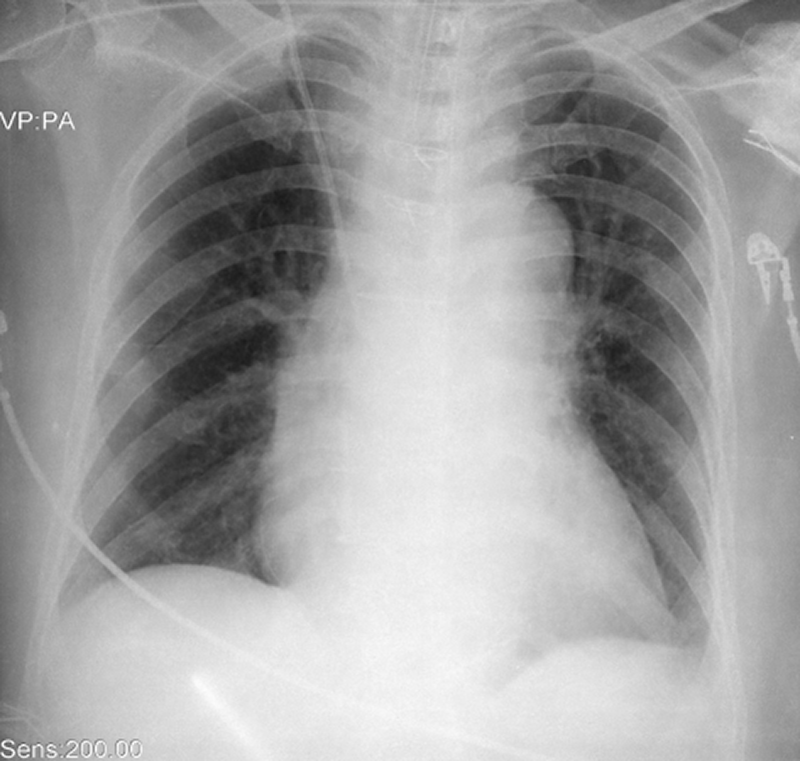

A 58-year-old male presents to the emergency room for severe leg pain x 2 hours. He is severely hypertensive and has no right femoral pulse on exam. He describes a severe episode of chest pain after using cocaine the previous night, which is mostly resolved now. Bedside US reveals a dissection flap in the aortic root prompting a CTA, confirming proximal dissection.